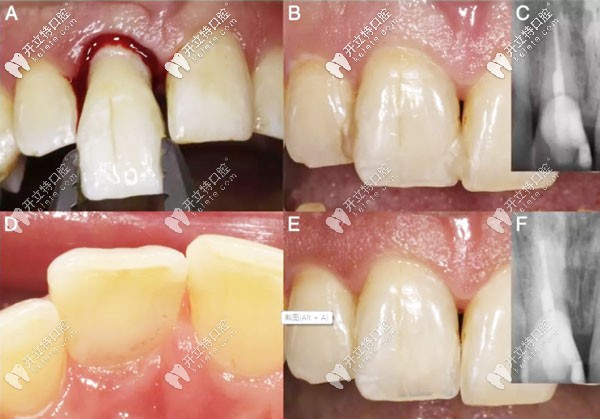

意向性再植術(shù)過程圖解

意向性牙再植術(shù)的預(yù)后示意圖